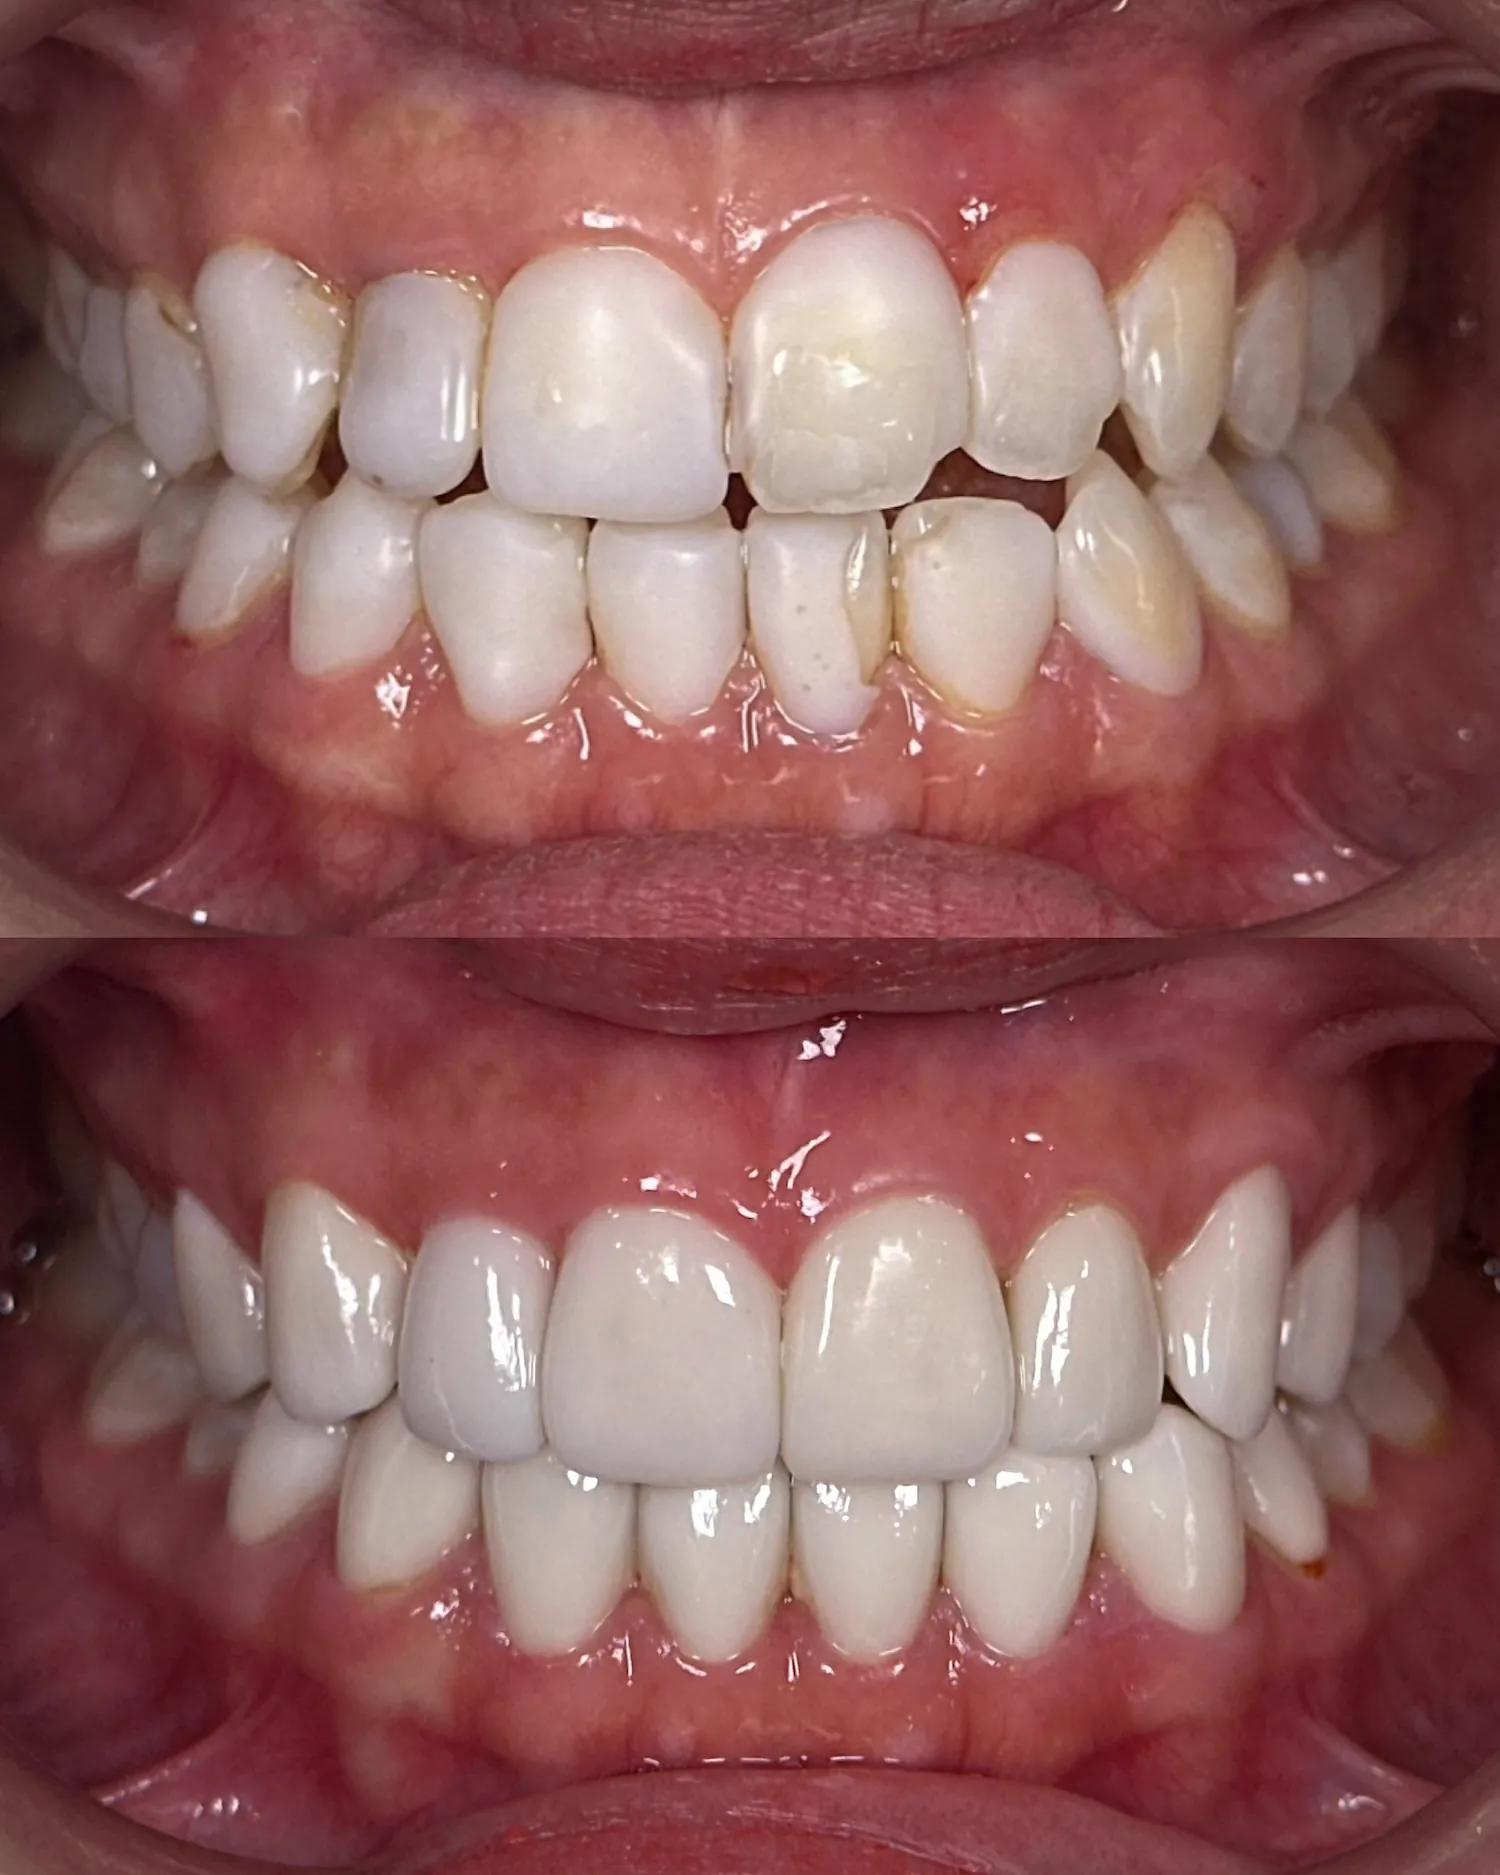

Invisalign®

As an award-winning Platinum Elite Invisalign provider, having completed over thousands of Invisalign® treatments, your smile is personally designed by our team of dentists for an aesthetically beautiful and functional end result using clear aligner technology to straighten your teeth.

Self Ligating Braces

Choose our self-ligating braces for a more comfortable orthodontic experience. Our innovative braces minimize discomfort and reduce treatment time. Enjoy fewer office visits and easier oral hygiene. Benefit from advanced technology and personalized care for effective, hassle-free orthodontic treatment. Unlock a confident smile with our self-ligating braces.